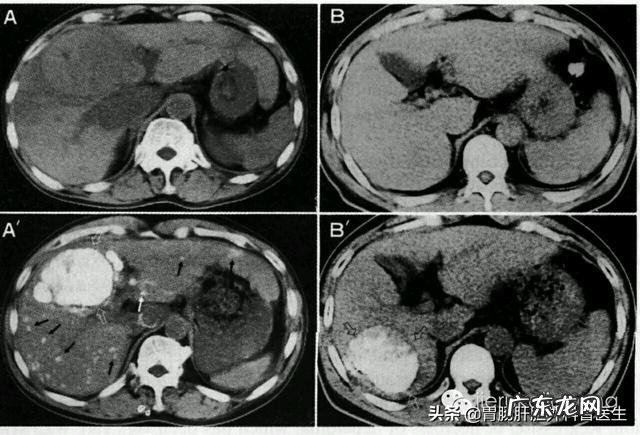

最近我就收了一个外伤脑出血的患者 , B超检查发现肝脏多发占位病变 , 后来做肝脏三期增强CT确定是肝癌 , 而且已经是晚期肝癌 , 没有手术机会的那种 。